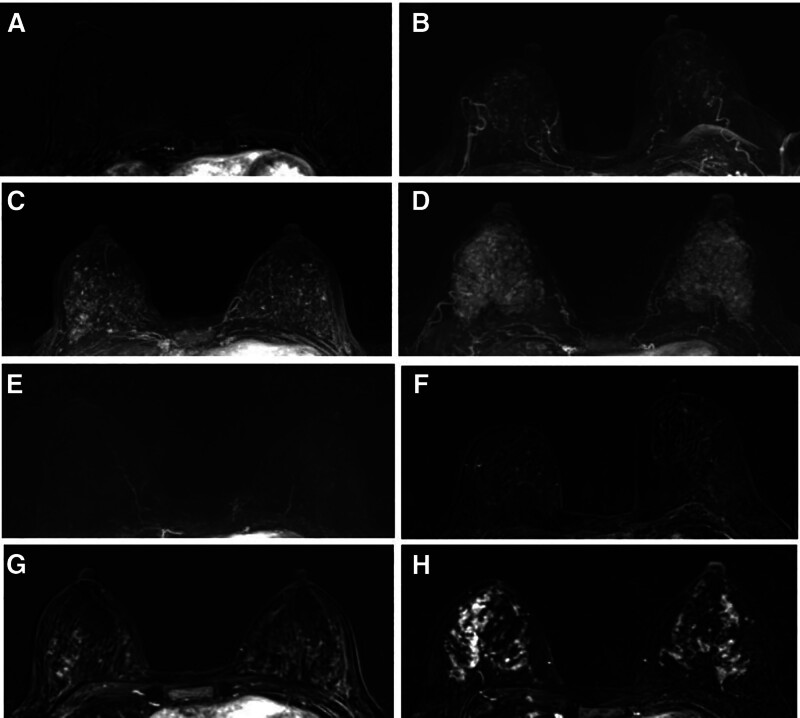

我们试图揭示乳腺癌(BC)风险与全场数字乳房x线摄影(FFDM)的乳房x线摄影密度(MD)和动态增强磁共振成像(MRI)的背景实质增强(BPE)之间的相关性。对2019年1月至2020年12月接受MRI和FFDM检查的216例女性进行了回顾性分析,其中72例BC经组织病理学鉴定。对照与BC病例按2:1匹配。FFDM患者的MD分为ACR a、ACR b、ACR c或ACR d。MR患者的BPE分为轻度、轻度、中度和显著4个级别。采用Logistic回归分析调查BC风险与BPE和MD之间的关系,得出比值比(or)。该研究对216名女性进行了回顾性研究,其中包括72例BC病例和144例正常对照。在BC病例中,64例患者被分级为ACR c或ACR d(88.9%), 40例患者被分级为中度或重度BPE(55.6%)。ACR c或d病例与ACR a或b的or分别为4.7和5.8 (P = 0.002)。与轻度或轻度BPE相比,表现出明显或中度BPE的or分别为5.0和3.3

We attempt to reveal the correlations between breast cancer (BC) risk with mammographic density (MD) in full-field digital mammography (FFDM) and background parenchymal enhancement (BPE) in dynamic enhanced magnetic resonance imaging (MRI). 216 women who received MRI and FFDM from January 2019 to December 2020 were reviewed, among which 72 BC cases were identified histopathologically. The control was matched with the BC case in 2:1. MD in FFDM were categorized as ACR a, ACR b, ACR c, or ACR d. BPE in MR was categorized into 4 grades, minimal, mild, moderate, or marked. Logistic regression analysis was utilized to investigate the associations between BC risk with BPE and MD, resulting in the odds ratios (ORs). The review was performed with a cohort of 216 women, including 72 BC cases and 144 normal controls. Among BC cases, 64 patients were graded as ACR c or ACR d (88.9%), and 40 patients were graded as moderate or marked BPE (55.6%). The ORs for ACR c or d cases versus ACR a or b were 4.7 and 5.8 for different readers, respectively (P = .002). The ORs for cases exhibiting marked or moderate BPE compared to mild or minimal BPE were 5.0 and 3.3 (P < .001). MD and BPE categories were identified as potential risk factors for BC. Increased levels of BPE or MD are strongly predictive of BC.